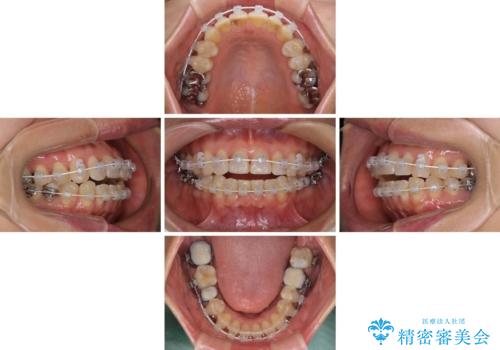

- 矯正装置

- 審美装置

- 治療期間

- 1年10ヶ月

- 前歯のデコボコを気にして来院された患者様です。

舌突出癖により、上下前歯がなかなか接触せずに治療期間を要しましたが、舌のトレーニングにより無事に治療を終えることができました。